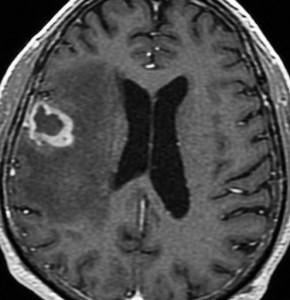

60代後半の患者さんで右前頭葉転移性脳腫瘍です。けいれん発作で発症しました。

定位放射線治療前

典型的な脳転移のMRIです。腫瘍は,リング状にガドリニウム増強され,内部が腫瘍壊死になっています。腫瘍周囲の脳浮腫がとても強いのが転移の特徴的画像所見(右側のT2強調画像)です。この転移巣に対して,35グレイ・5分割の定位放射線治療が加えられました。

2年後 放射線壊死の進行

定位放射線治療後約2年,前の画像からはわずか3ヶ月後のMRIです。また右前頭葉の転移病巣が再発したかのように見えます。周囲の浮腫も広がって,左の片麻痺が悪化しました。しかし,ガドリニウム増強されて白くリング状に写る部分が不整形でまわりがギザギザしています。ステロイドを投与しましたが改善せずに悪化傾向を示しました。